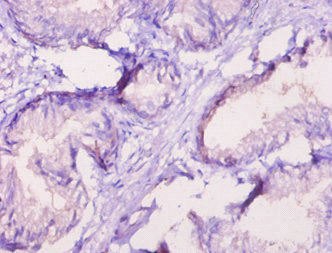

Immunohistochemistry of paraffin-embedded human prostate tissue using CSB-PA020067LA01HU at dilution of 1:10